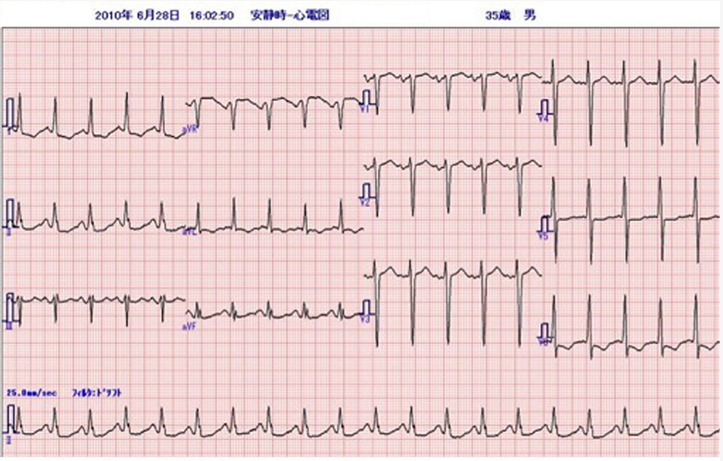

心電図

問題の心電図は洞頻脈、V1で典型的な左房負荷の所見を認め、左室の電位は高く、左室誘導(I、aVL、V5−6)でsagging型のST低下とT波の逆転を認める。典型的な圧負荷に対する左室肥大の所見である。左房負荷の存在から長期間の圧負荷と左心不全の存在が示唆される。来院時の身体所見は、血圧が高く頻脈。心臓では3音、4音がsummation gallopとして聴取されている。急性左心不全による肺水腫の状態である。胸部X線では、心陰影は拡大、左室の拡大と肺血管の再分布を認める。